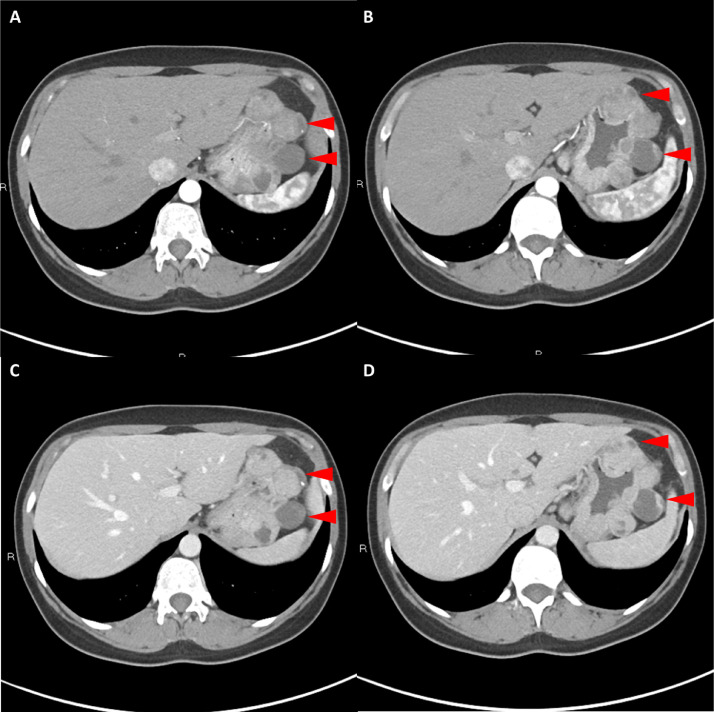

胸部、腹部和骨盆的對(duì)比增強(qiáng)動(dòng)脈和靜脈期 CT 顯示多個(gè)圓形、主要是血管豐富的異質(zhì)腫塊,具有囊性和實(shí)性成分,起源于胃底和胃體(圖 2-4)。 病變部分呈外生結(jié)構(gòu),被認(rèn)為位于粘膜下層。 在頸部多發(fā)同步性副神經(jīng)節(jié)瘤的情況下,賊初的鑒別診斷包括多發(fā)性副神經(jīng)節(jié)瘤、多發(fā)性 GIST 以及轉(zhuǎn)移性疾病。

Fig. 2

圖 2:多發(fā)胃腸道間質(zhì)瘤的軸位 CT 圖像。 (A 和 B)軸位動(dòng)脈相增強(qiáng) CT 圖像和(C 和 D)軸位靜脈相增強(qiáng) CT 圖像顯示多個(gè)圓形、不均勻、增強(qiáng)的腫塊,具有實(shí)性和囊性成分。 腫塊位于粘膜下,結(jié)構(gòu)呈外生。

Fig. 3

圖 3:多個(gè)胃腸道間質(zhì)瘤的冠狀和矢狀圖像。 (A 和 B)冠狀動(dòng)脈相對(duì)比增強(qiáng) CT 圖像顯示胃賁門(mén)產(chǎn)生的外生性腫塊。 (C 和 D)矢狀動(dòng)脈相位對(duì)比增強(qiáng)圖像顯示腫塊的異質(zhì)性和外生結(jié)構(gòu)。

Fig. 4

圖 4: 胃腸道間質(zhì)瘤的三維表示。 (A 和 B)胃腸道間質(zhì)瘤在動(dòng)脈期和冠狀面的 3D 可視化提供了進(jìn)一步的解剖細(xì)節(jié)和空間信息。